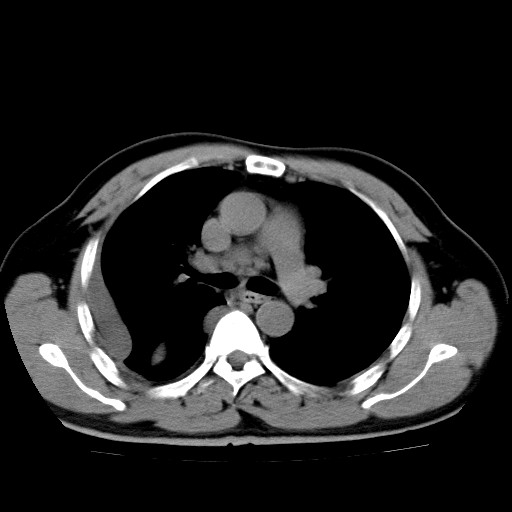

男,54岁,咳嗽,右侧胸痛10天。肺窗>150k,传不了

右肺中心型肺癌并右下肺不张,右侧胸膜纵隔转移。

右中央型肺癌并右肺下叶不张,纵隔内及右胸膜转移,右胸腔积液

考虑   右肺癌伴右下肺部分不张,阻塞性肺炎,纵隔淋巴结增大,右侧胸腔积液其他待排

考虑右肺下叶中央型肺癌并右肺下叶不张,纵隔淋巴结内及右胸膜转移。建议增强。

右下叶大片实变,肺门未见明显肿块影。有胸腔积液和纵隔内肿大淋巴结影。没有增强和肺窗,不好定。

考虑:1、右下叶周围型肺癌伴胸膜、纵隔淋巴转移?